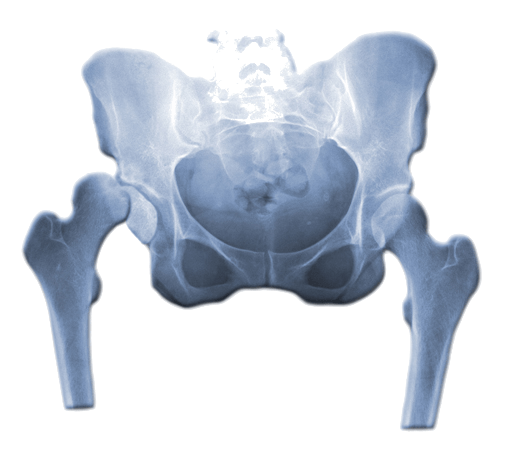

Dysplazja stawu biodrowego

Dysplazja stawu biodrowego to wada wrodzona polegająca na wadliwie ukształtowanym biodrze. Jest to patologia, która może występować w dwóch odmianach – jako czysta dysplazja, cechująca się tylko wadliwym ukształtowaniem biodra, jak również jako dysplazja z przemieszczeniem głowy kości udowej poza panewkę, co nazywane jest wrodzonym zwichnięciem stawu biodrowego. Wczesne wykrycie dysplazji stawu biodrowego i odpowiednio wcześnie podjęte leczenie daje szansę pełnego wyleczenia.

Dysplazja stawu biodrowego to stan, w którym staw biodrowy nie rozwija się prawidłowo, co prowadzi do jego niestabilności i zwiększonego ryzyka zwichnięcia. Schorzenie to może wystąpić na każdym etapie życia, od niemowlęctwa do dorosłości, ale najczęściej rozpoznawane jest u niemowląt i małych dzieci.